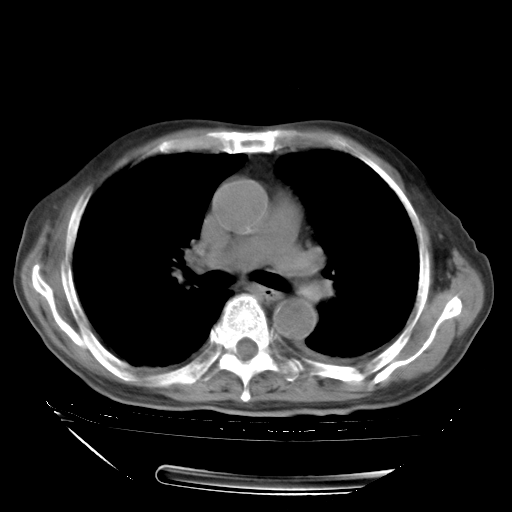

经过24天治疗,岳父的病情基本稳定。生活基本可以自理,可以下床活动。呼吸困难早已消失。体温基本正常。

只是甲强龙用80mg时血小板升到正常,改为60mg后又降到63×10*9/L。

主要治疗甲强龙80mg×14天,60mg×10天;同时抗结核(异烟肼+利福平+乙胺丁醇)。环磷酰胺0.1 tid 10天。

特别感谢胡教授、高管、桃子版主给出关键的治疗建议。桃版把所有肺部影像和全部临床资料请所在医院呼吸科、感染病科、结核科、临床免疫科专家会诊。临床免疫科专家制定了完整的治疗方案。